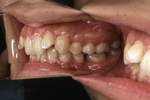

矯正の症例

1) 矯正前の状態

叢生(そうせい…歯がデコボコしたり、重なりあって生えていたりする状態)

開咬(かいこう…奥歯はしっかり噛んでいるが、上下の前歯が噛まずに隙間がある状態)